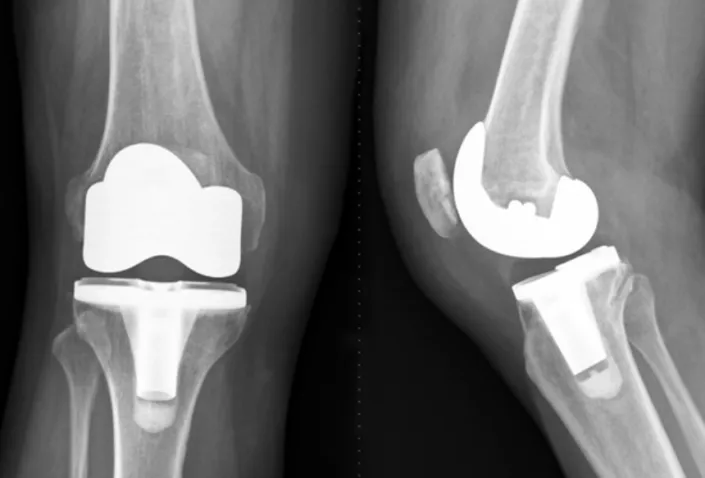

全膝關節置換術(Total knee replacement, TKR):將受損的膝關節全部更換成人工膝關節。

半膝關節置換術(Unicompartmental knee replacement, UKR):只更換膝關節中的一部分,通常是內側或外側的一個區域。需要保留膝關節的其他部分,減少手術風險和恢復時間。

髕股人工關節置換手術(Patellofemoral arthroplasty, PFA):專門更換膝蓋骨和股骨之間的關節,不是整個膝關節。用於那些只有膝蓋骨和股骨之間的膝關節受損的人。